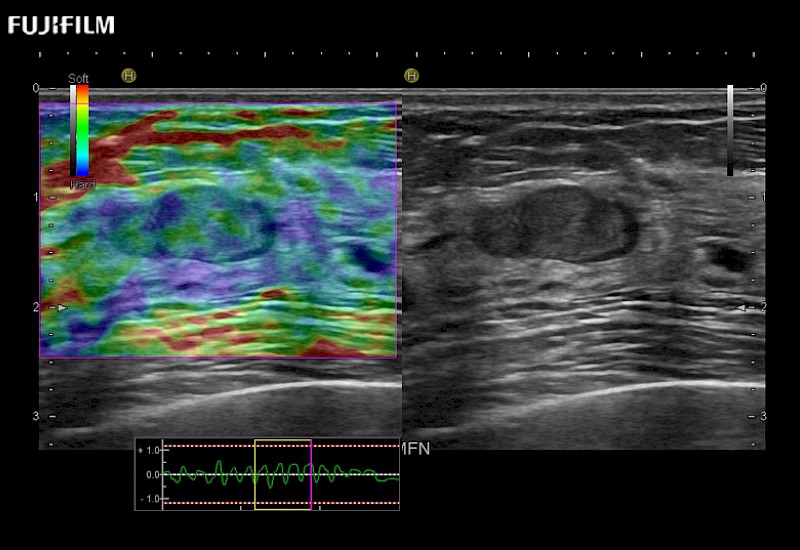

The ARIETTA 750 incorporates all of the proven technologies and functions that medical professionals have come to expect from Fujifilm Healthcare.

ARIETTA 750 is the definitive diagnostic ultrasound solution for any clinical setting - Private Office, Imaging Center, or Hospital. The ARIETTA platform provides the ultimate in clinical performance with its state-of-the-art features and large user-friendly display.

The ARIETTA 650 DI combines trusted Fujifilm Healthcare technologies and features tailored for surgical oncology.

Designed to meet the demands of surgeons, the ARIETTA 650 DI offers precise guidance. Its advanced capabilities and large, intuitive display offer accurate and efficient care in operating rooms and specialized surgical settings.